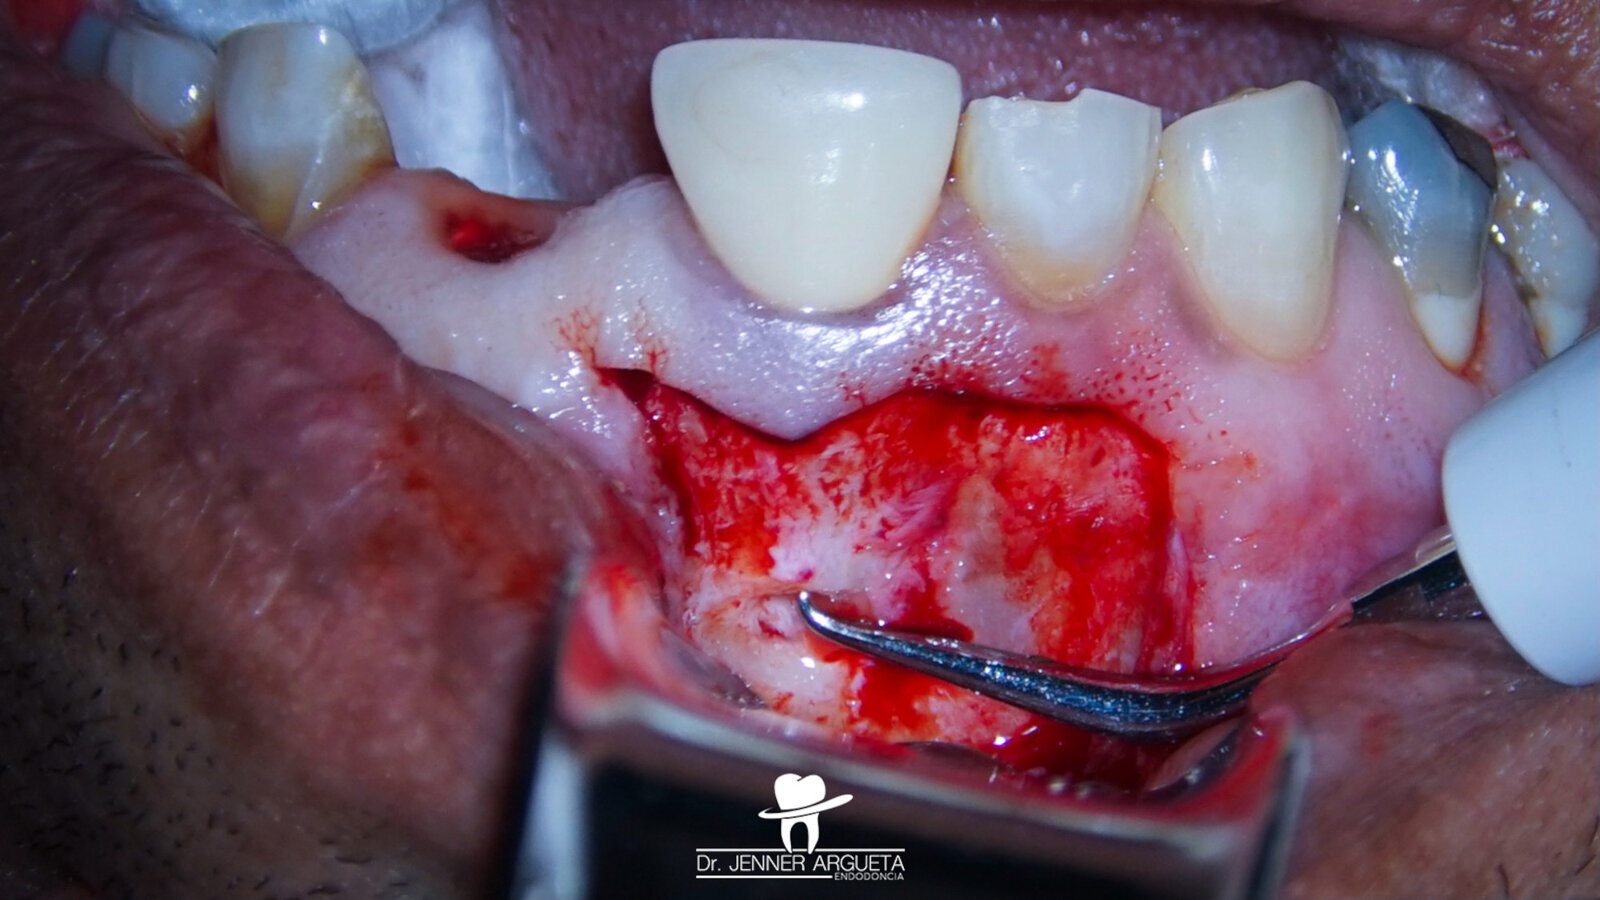

Tooth #21 was extracted, and a bone grafting material (DM Bone, Meta Biomed) was placed in the area to prepare the site for receiving an implant in the future (Fig. 10). Four weeks after the extraction, periapical surgery was performed on tooth #11, and the minimum amount of root was resected in order to avoid compromising the crown–root ratio. The retro-cavity was prepared using ultrasonic tips (Fig. 11), and CeraPutty was used to retro-obturate the root (Figs. 12 & 13). The sutures were removed five days after surgery (Fig. 14a–c). The four-month follow-up radiograph showed the process of healing in both treated areas (Fig. 15).

Fig. 12: Retro-obturation of tooth #11 during periapical surgery using CeraPutty.

Figs. 14a–c: Post-op suturing sequence. Immediate post-op suturing (a). Five-day follow-up clinical image, just before the suture removal (b). Clinical image immediately post-suture removal, showing good healing of the area (c).